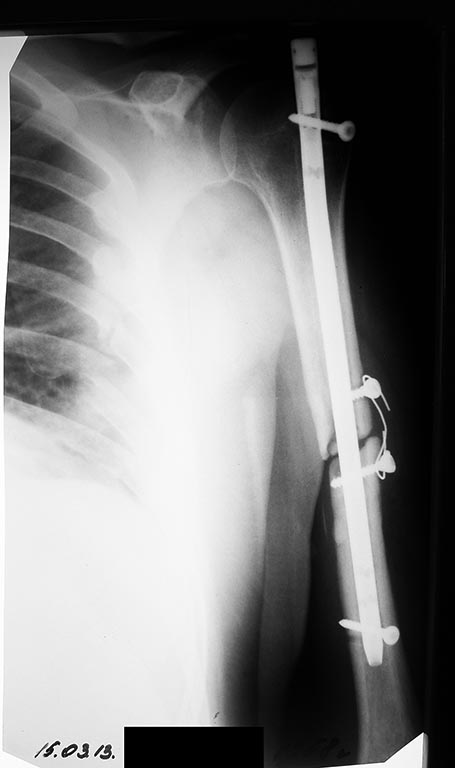

Б-ой П 54 года. г Алапаевск.Травма 25.09.2012. 27.09.2012 - Остеосинтез

левого плеча стержнем Кюнчера. Воспалительных реакций после операции не

было. Через 3 мес - 25.12.2012 повторная операция - Остеосинтез левого

плеча стержнем с блокированием. Воспалительных реакций после операции не

было.Поступил в травматологическое отделение Госпиталя с жалобами на:

сохраняющуюся слабость в левой верхней конечности. Общие анализы крови и

мочи спокойные (эр - 4,7; Тромб - 284; Лейк - 5,1; сегм - 55; лимф - 36;

СОЭ - 6). Планируется удалить конструкции, установить чрескостной

спицевой аппарат.